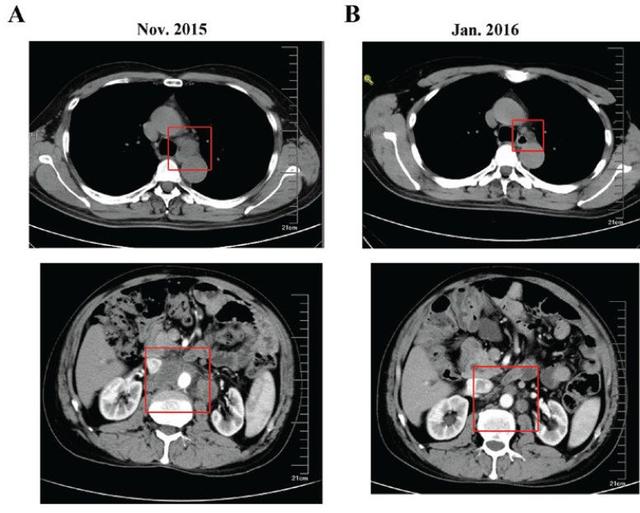

2015年11月,复查CT:纵隔、腹膜后淋巴结转移(图3)。

2016.01,复查CT示纵隔、腹膜后淋巴结缩小(图3),肿瘤标志物降低(图5)。